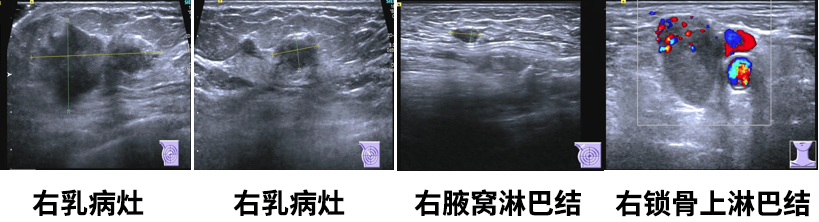

乳腺彩超

1.右乳肿物(约5.0*2.4*4.7cm),乳腺癌可能,BI-RADS5;

2.左乳切除术后,左胸壁未见明显异常;

3.右腋下(1.0*0.5cm)及右侧锁骨上淋巴结(2.6*1.8cm),转移可能。

乳腺MR

右侧乳头后侧中部多个异常信号结节(较大者23*15mm),符合乳腺癌,BIRADS:5类。右侧腋下肿大淋巴结,考虑转移。

乳腺浸润性小叶癌。IHC:ER约95%强(+)、PR约1%中等(+)、Her-2(2+)、Ki67热点区约15%(+)、GATA-3(+)、CK5/6(-)、P120浆(+)、E-cadherin(-)。HER2 FISH(-)。

右腋下淋巴结穿刺

见癌巢浸润,乳腺浸润性小叶癌转移可能性大。IHC:ER约95%中等-强(+)、TRPS1(+)、GATA-3(+)、CK5/6(-)、E-cadherin(-)、CgA(-)、Syn(-)。

右锁骨上淋巴结细针穿刺

见癌细胞。IHC:CK5/6(+)、P40(+)、TRPS1弱(+)、GATA-3个别弱(+)、E-cadherin膜(+)、P120膜(+)、ER(-)、PR(-)、HER-2(-)、CDX2(-),结合细胞形态和对比既往病理,考虑为鳞状细胞癌或伴有鳞状分化的癌可能性大。